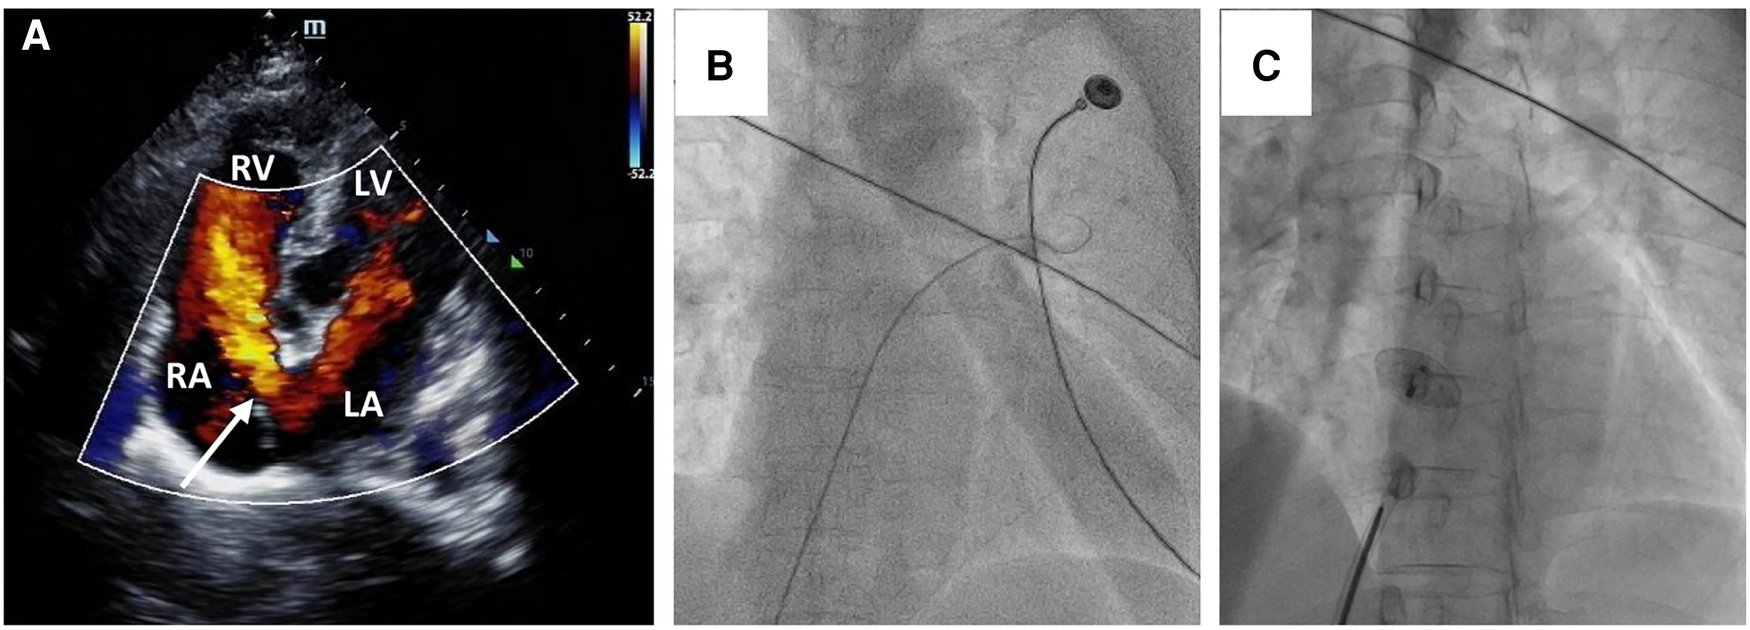

Figure 1

Secundum-type ASD finding and percutaneous secundum-type ASD closure. Transthoracic echocardiography revealed about 22 mm ASD (white arrow) with shunt flow from left atrium to right atrium (A) The intraoperative fluoroscopy showed that the guidewire passed through the inferior vena cava and the right atrium sequentially, and then through the defect site to the left atrium (B); a 24 mm ASO device was successfully deployed in the ASD (C).